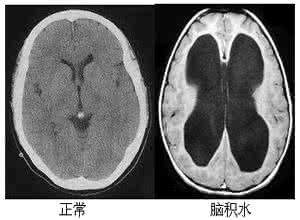

腦積水主要是由于顱腦內(nèi)出現(xiàn)了各種病變或者是疾病性使腦脊液分泌的情況過多,存在了吸收障礙性的情況下,就會(huì)導(dǎo)致顱內(nèi)腦脊液量出現(xiàn)增加的情況,而慢慢使腦室系統(tǒng)出現(xiàn)擴(kuò)大或者是蛛網(wǎng)膜下腔位置處有擴(kuò)大的一個(gè)癥狀性,是會(huì)導(dǎo)致各種身體出現(xiàn)連鎖方面的癥狀性。